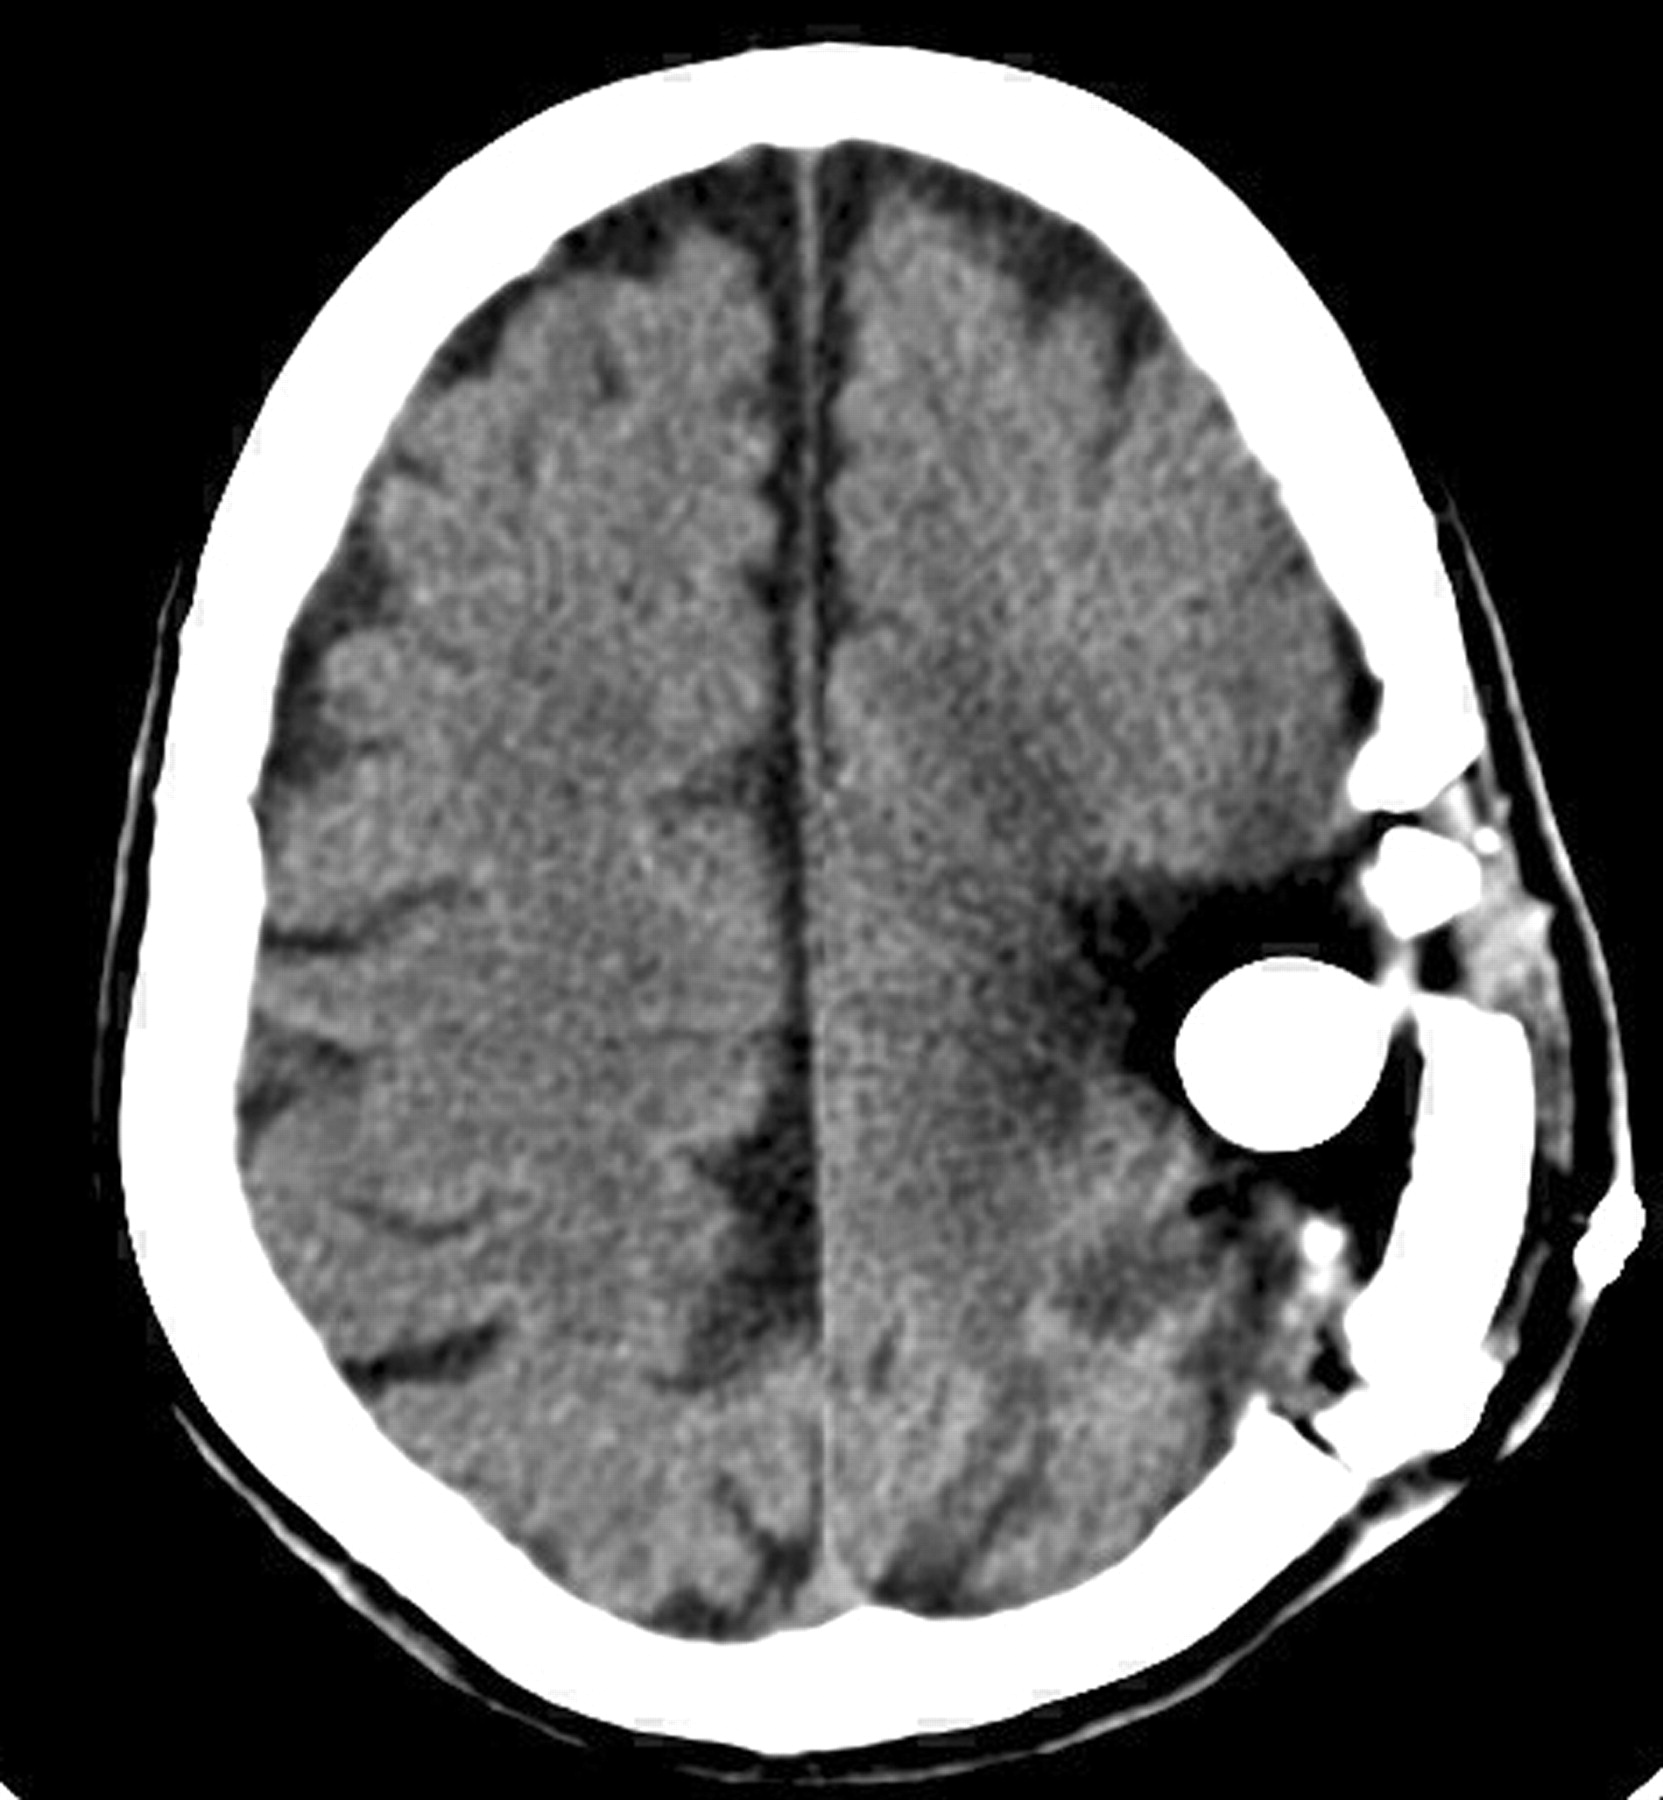

In all patients, the GSRTS device was clearly identified. The balloon was hyperattenuated on CT scans (Fig 2), reflecting the iodinated contrast material. It had low signal intensity on T1-weighted and FLAIR MR images and high signal intensity on T2-weighted MR images (Fig 3). On one CT study, the brain immediately around the balloon could not be seen because of artifacts (Fig 2). On all MR imaging studies, the brain adjacent to the balloons was well depicted with all sequences (Fig 3).

CT scan obtained <48 hours after device implantation shows the attenuating balloon filled with iodinated contrast material, with artifacts obscuring tissues around it.